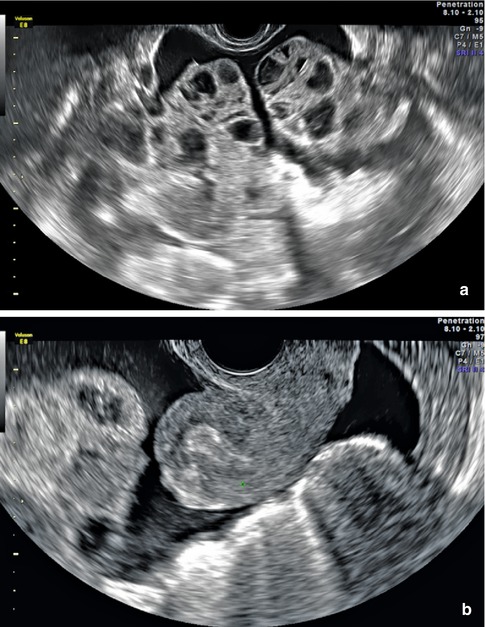

Pelvic Ultrasound Scan Of A 26 Year Old Pregnant Patient With Ovarian Download Scientific Diagram